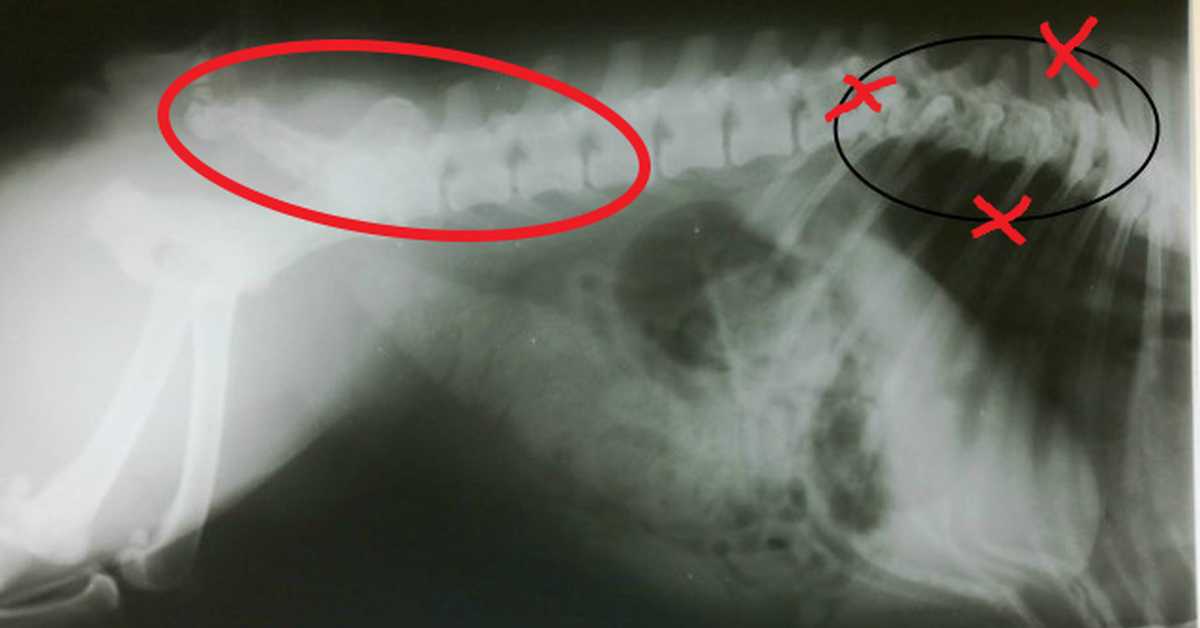

Заболевания позвоночника у домашних животных: диагностика и лечение

Раздел: Визуальные истории